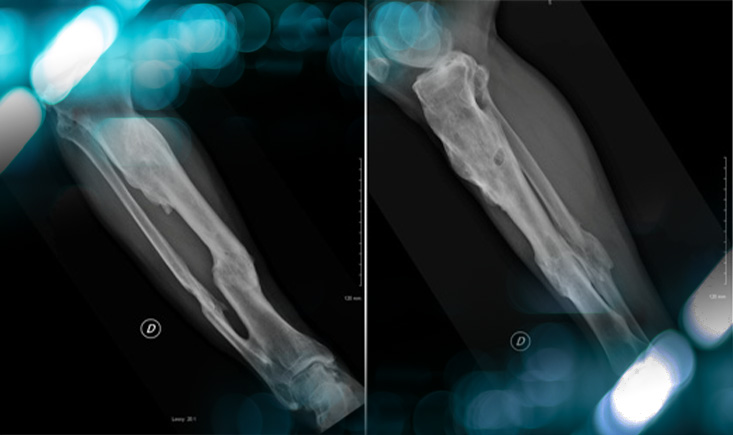

Clinical presentation

• Male, 67 years old

• Complex open leg fracture >20 years ago, complicated by infection and skin disorders

• Tricompartmental knee osteoarthritis resistant to conservative treatment

Clinical examination:

• Skin relatively supple

• ROM 0/5/110

• Varus deformity ~20°, partially reducible

• Lateral laxity in extension and at 30° of flexion

• Lateral joint opening during gait

Imaging

Management-of-Total-Knee-Arthroplasty-in-Post-Traumatic-Malunion-figure1

Management-of-Total-Knee-Arthroplasty-in-Post-Traumatic-Malunion-figure2